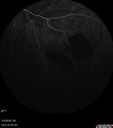

51 year old male with a broken vein in the left eye. His vision is pretty good. He has not noticed any vision change. You asked him to come here for further evaluation in the left eye. VA OD: sc20/63 PH20/25-2 NccJ1 VA OS: sc20/20 Patient had scatter laser to non-perfused retina and never had a vitreous hemorrhage (yet)

Coats' Disease -51 year old asymptomatic male450 views20/20 vision - had laser to non-perfusion because of proliferation.00000